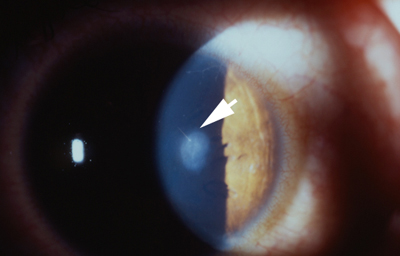

Fotos 1 - Picadura en el Limbo temporal

Postoperatorio con edema de córnea que fue cediendo progresivamente. - Polo posterior sin alteraciones.- Tensión Ocular 12 aplanático de Goldman

A los 5 meses: Refracción: AVsc 1.00 +0.50 esférico AVcc 1.00. Discreto engrosamiento corneal en creciente, inferior-temporal. - Despigmentación del Iris, pupila normoreactiva. Tensión ocular 12 aplanático de Goldman.

Último control a los 24 meses. Refracción: AVsc 1.00 +0.75 esférico AVcc 1.00. Subjetivamente Bien. - Creciente corneal inferior engrosado con mayor textura en la Descemet. (Foto No2)

Foto 2 - Ultimo control a los 24 meses